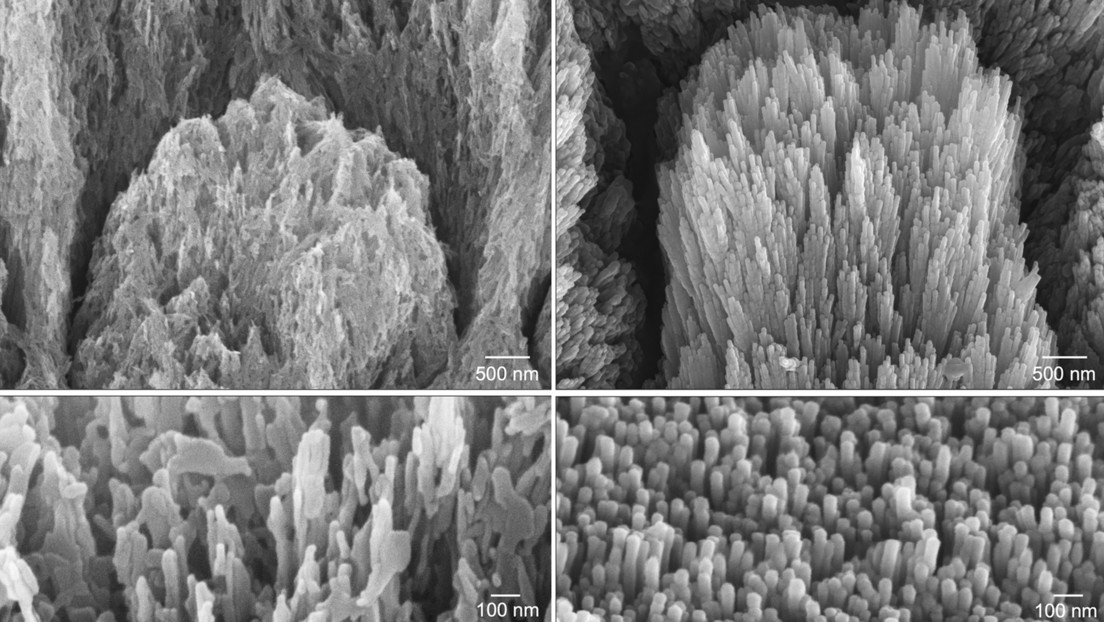

El nuevo aparato evita estos inconvenientes gracias a un método no invasivo basado en una sonda óptica que se aplica a la superficie del diente. El dispositivo registra la fluorescencia del tejido y envía la información a un ordenador, donde un modelo de aprendizaje automático determina al instante el tipo de dentina.